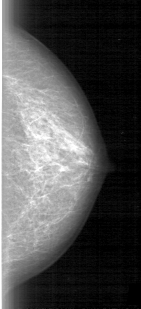

D_4012_1.RIGHT_CC

RIGHT_CC LINES 5281 PIXELS_PER_LINE 2086 BITS_PER_PIXEL 12 RESOLUTION 43.5 OVERLAY